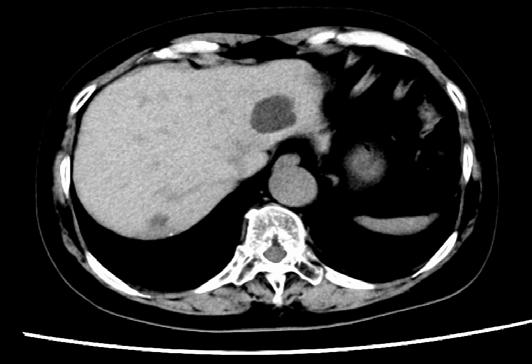

I hope these insights inspire curiosity, collaboration, and compassion, reminding us why we do this work. I hope to see you in Chicago, Illinois, for ASCO 2026.

Chair, ASCO 2025 Annual Meeting Scientific Program Committee; Director, Breast Cancer Research, Sarah Cannon Research Institute, Nashville, Tennessee, USA